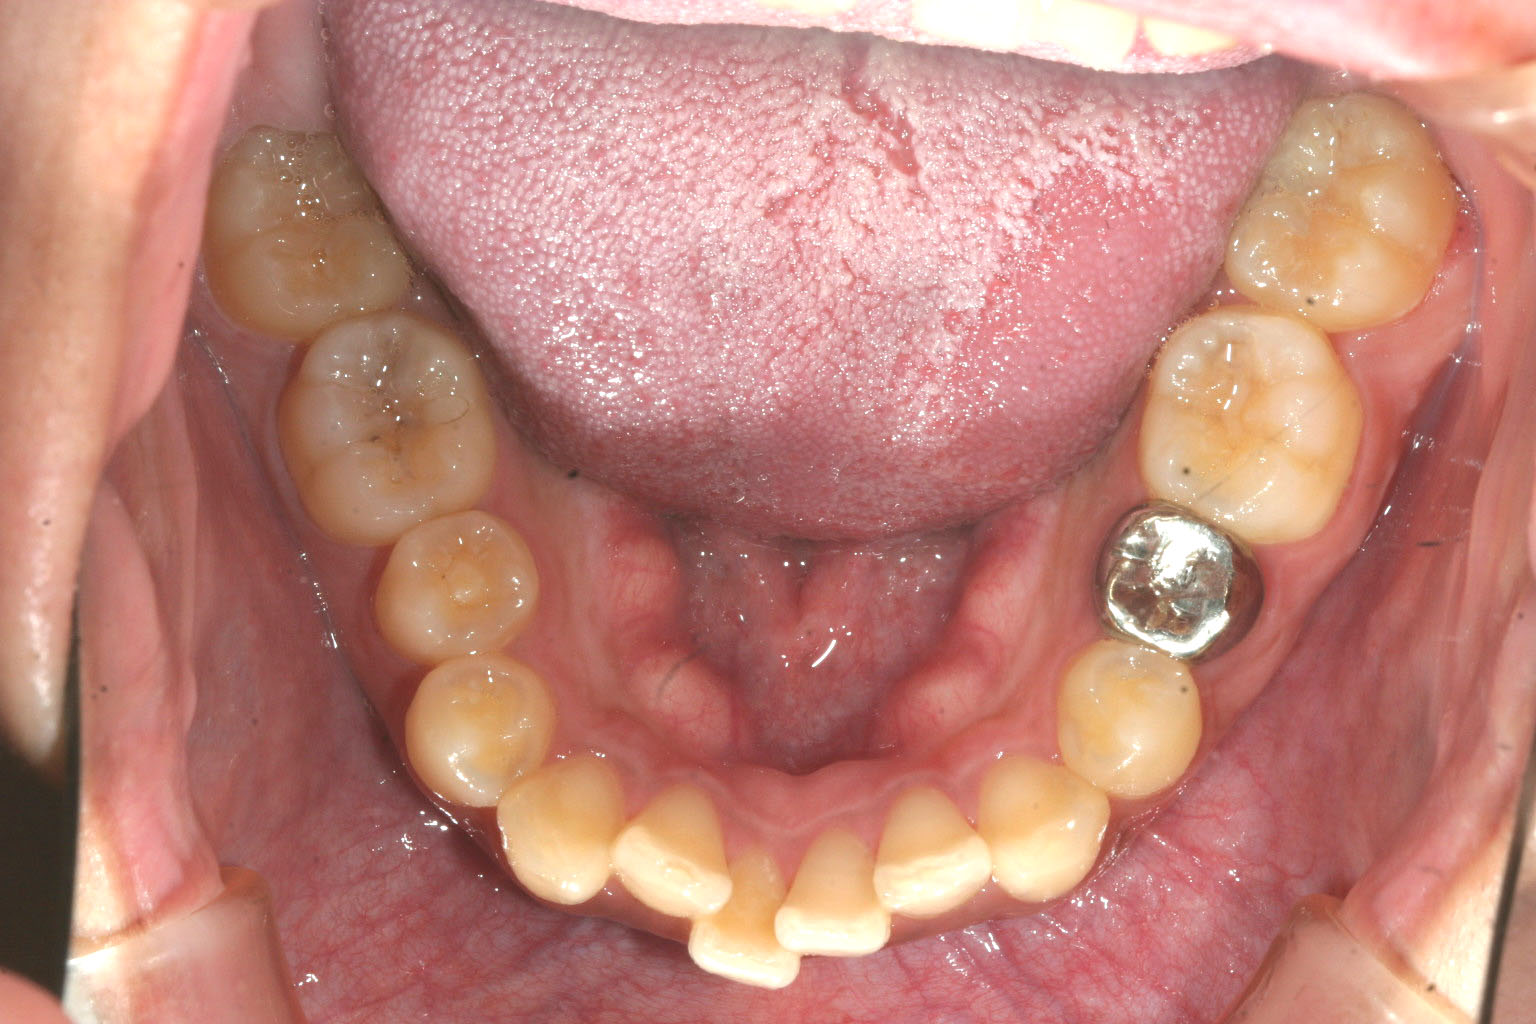

下顎のアーチが狭く前歯部に叢生が目立ちます。

下顎も綺麗に改善しました。